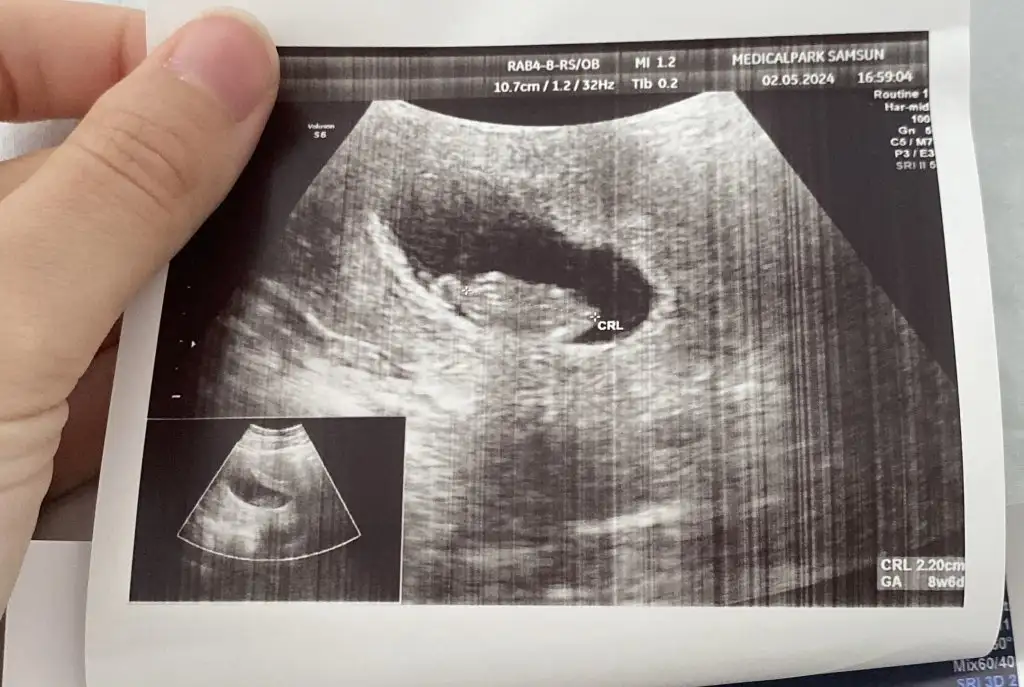

Çok şükür canım <3 Hadi buyrun bakalım tahminciler, bize şak diye yapıyordunuz sağda mı solda mı bakıp, tam ortada duran ne oluyor şimdi shdksakdhkSelam kızlar kontrolden geldim , çok şükür kalp atımını dinledik . Progestona devam dedi doktorum. Cinsiyet tahmini yapabilir misiniz biraz daha büyümüşken

Haa o da doğru benimki nerde ya ortada gibiAma bence bu solda. Yani ayna görüntüsü bu gördüğümüz ki ben soldan yumurtlamıştım takipli olduğum için biliyordumYanlış anlaşılmasın erkeğe de okeyim sonuçta ikisi de yok elimizde de içimden kız geçiyor

Canım şöyleymiş embriyo solda olduğunda karın ultrasonunda sağda görülürmüş. Yani bu soldaymış evet ve solda olduğunda kabule göre erkek oluyormuşHaa o da doğru benimki nerde ya ortada gibi

Canım şöyleymiş embriyo solda olduğunda karın ultrasonunda sağda görülürmüş. Yani bu soldaymış evet ve solda olduğunda kabule göre erkek oluyormuşSeninkine bakalım bi...

Ama aynı durum için bana erkek dedin az önce :)seninkide sağda işte.yani normalde solda . buda kız demek oluyor. yani bence